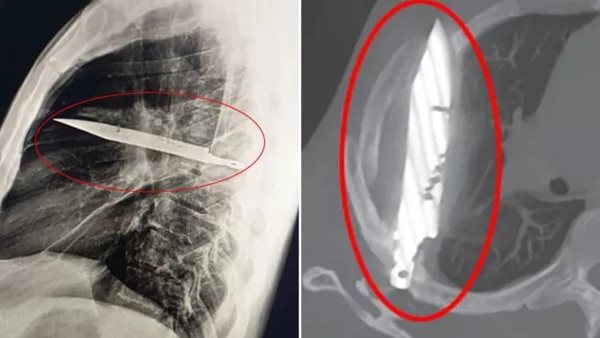

اكتشف أطباء في تنزانيا أن رجلا يبلغ من العمر 44 عاما، كان يعيش منذ 8 سنوات بسكين كبيرة عالقة في صدره دون أن يدري، ومع شعوره بالألم راجع المستشفى بسبب إفرازات قيحية في صدره، وذلك وفقًا لـ ذا صن.

الأطباء يعثرون على سكين عملاقة عالقة في صدر مريض منذ ثماني سنوات

الفحوص الأولية لم تُظهر أي أعراض خطيرة، لكن صور الأشعة السينية كشفت مفاجأة مذهلة: شفرة سكين مغروسة قرب لوح كتفه الأيمن، نجت بأعجوبة من إصابة أي عضو حيوي، الرجل أوضح أنه أصيب خلال شجار عنيف قبل نحو عقد، تلقى بعده علاجًا للجروح الظاهرة، ولم يشعر منذ ذلك الحين بأي مشاكل حتى ظهور القيح مؤخرًا.

وأجرى الأطباء عملية جراحية دقيقة لاستخراج الشفرة وتصريف الصديد الناتج عن النسيج التالف، ونجح المريض في التعافي بعد البقاء يومًا في العناية المركزة وعشرة أيام في الجناح العام، ونُشرت تفاصيل الحالة في مجلة تقارير الحالات الجراحية الشهر الماضي.